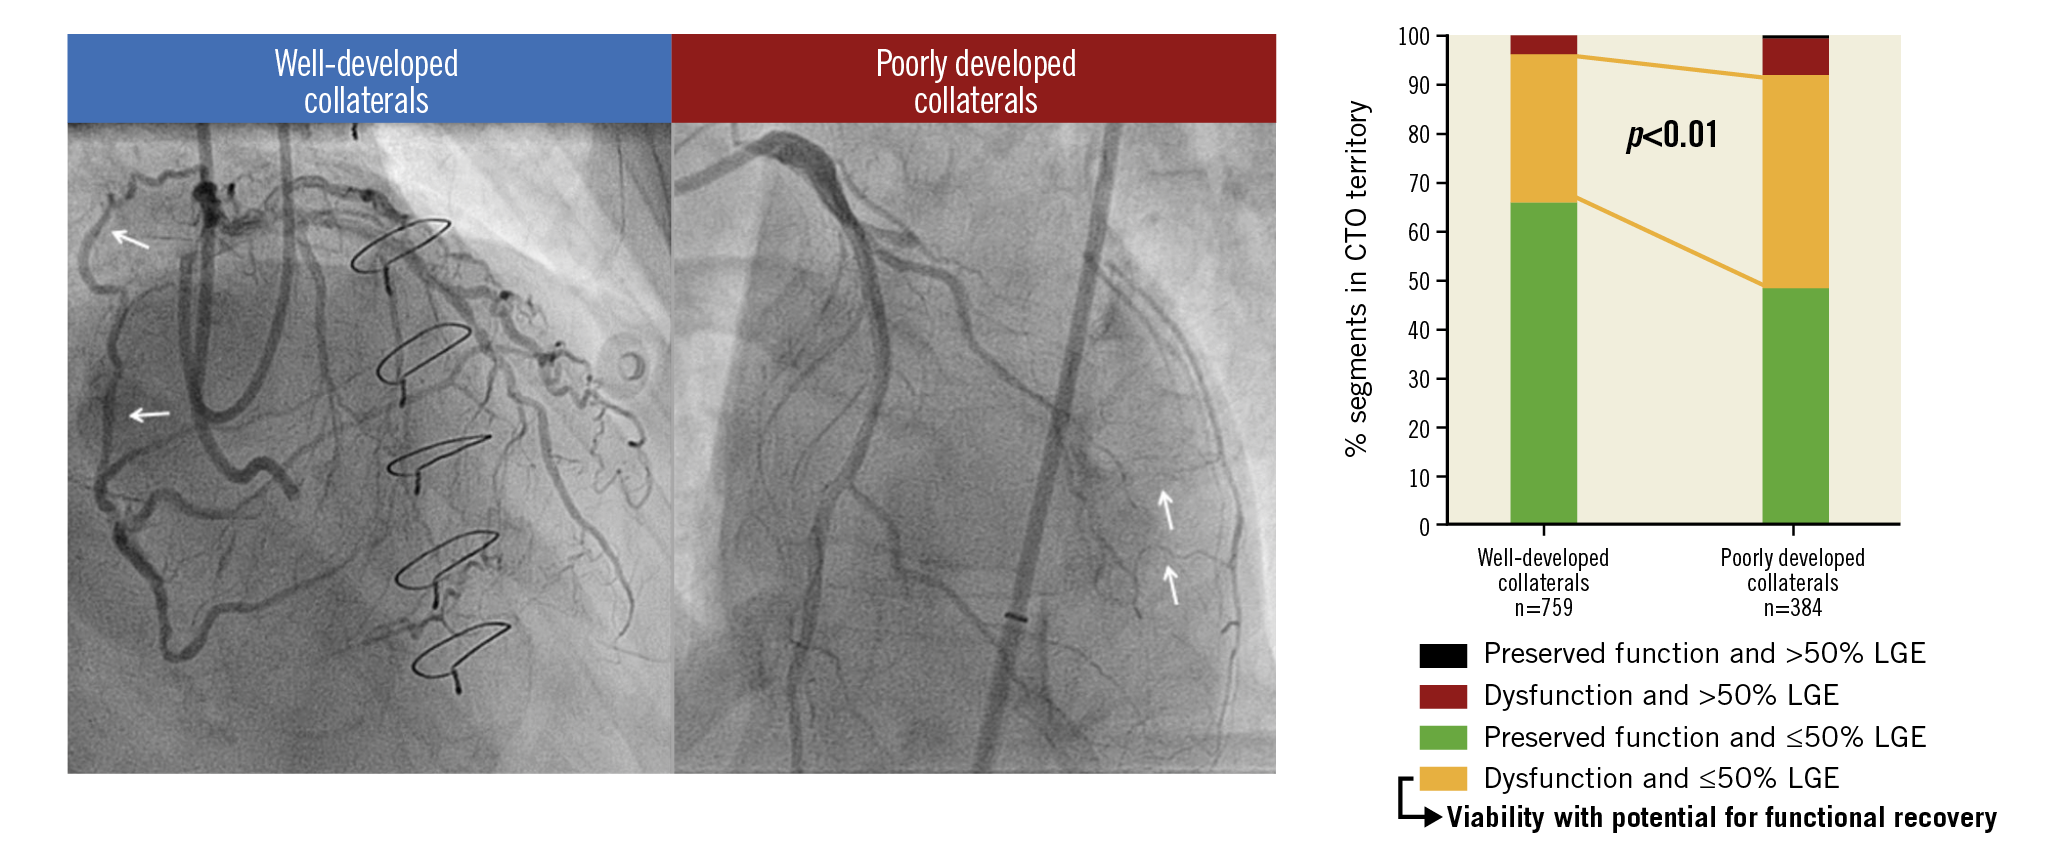

Visual summary. CMR-derived viability with potential for functional recovery is regularly present in myocardium supplied by poorly developed collaterals in patients with a CTO.

Absence of or ≤50% LGE was observed in 1,085 out of 1,143 (95%) segments in the CTO territory. Dysfunctional myocardium was present in 455 (40%) segments, with the other 688 (60%) demonstrating preserved function. Extent of scar and SWT in CTO segments were inversely correlated (Figure 3C). Viability, represented by dysfunctional myocardium without extensive scar, was present in 399 (35%) CTO segments. As shown in Figure 4A, Figure 4B, and Supplementary Table 4, CTO-related segments were analysed in all patients and in patients stratified according to documented CTO vessel-related history of MI and presence of scar in the CTO territory on CMR. In patients with WD collaterals, the prevalence of no or limited scar was higher compared to patients with PD collaterals (731 out of 759 [96%] vs 354 out of 384 [92%] segments, p<0.01), although differences were small. Myocardium was dysfunctional in a substantially higher number of segments in patients with PD collaterals compared to patients with WD collaterals (196 out of 384 [51%] vs 259 out of 759 [34%] segments, p<0.01). As a consequence, viability was present in more segments among patients with PD collaterals compared to patients with WD collaterals (168 out of 384 [44%] vs 231 out of 759 [30%] segments, p<0.01) (Figure 4C, Figure 4D). In addition, more CTO segments were dysfunctional in patients with multivessel disease compared to patients with single-vessel disease, leading to a higher number of segments with viability (Supplementary Table 3).

Figure 4. Distribution of CTO segments according to myocardial contractility and (non-)extensive scar formation. Numbers below the horizontal axis represent number of segments. A) CTO segments in all patients and in subgroups of patients stratified according to documented CTO vessel-related history of MI and presence (or absence) of scar in the CTO territory on CMR. B) Percentage of segments demonstrating viability with potential for functional recovery, compared among subgroups. C) Distribution of CTO segments according to collateral status. D) Percentage of segments demonstrating viability with potential for functional recovery compared between patients with WD collaterals and those with PD collaterals. CMR: cardiac magnetic resonance; CTO: chronic coronary toatal occlusion; MI: myocardial infarction; PD: poorly developed; WD: well-developed

The present study is the largest to date evaluating the extent of myocardial infarction, function and viability assessed with CMR in patients with a CTO. The findings were additionally related to the presence of WD and PD collaterals on invasive coronary angiography. The infarcted area in the CTO territory was generally limited, with extensive scar observed in only 5% of CTO segments. Well-developed collaterals were associated with less scar and more preserved function in myocardium subtended by a CTO. Myocardial viability in the CTO territory with potential to recover functionally after revascularisation, in this study represented by dysfunctional myocardium without extensive scar, was more extensive in patients with PD collaterals.